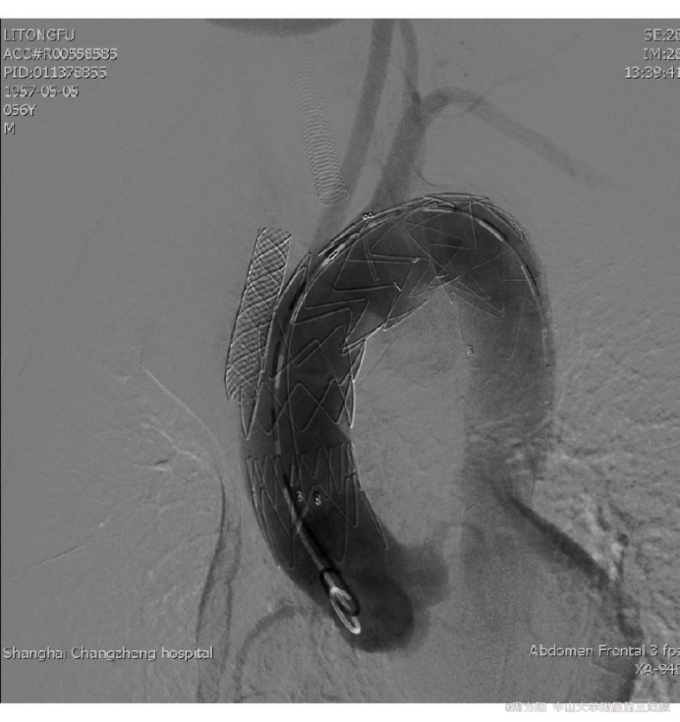

术后6个月后随访,声音嘶哑无复发,复查血清TRUST试验下降至1∶32,主动脉CTA:血管支架植入术后改变,支架植入处血管瘤消失。患者梅毒损害累及心血管系统属于三期梅毒,属于梅毒远期并发症,同时三期梅毒还常表现在神经、胃、眼、耳受累及树胶肿损害等。1009-7708(2014)05-0415-05